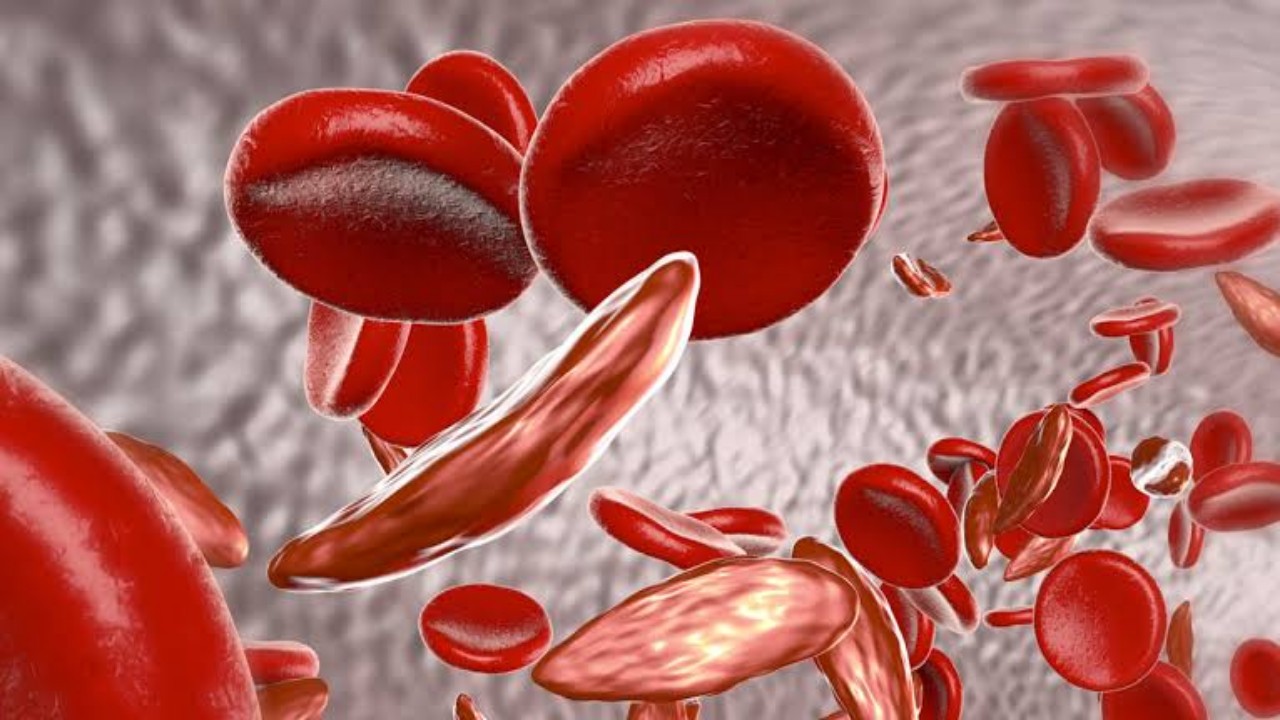

أعراض الأنيميا المنجلية وطرق الوقاية منها